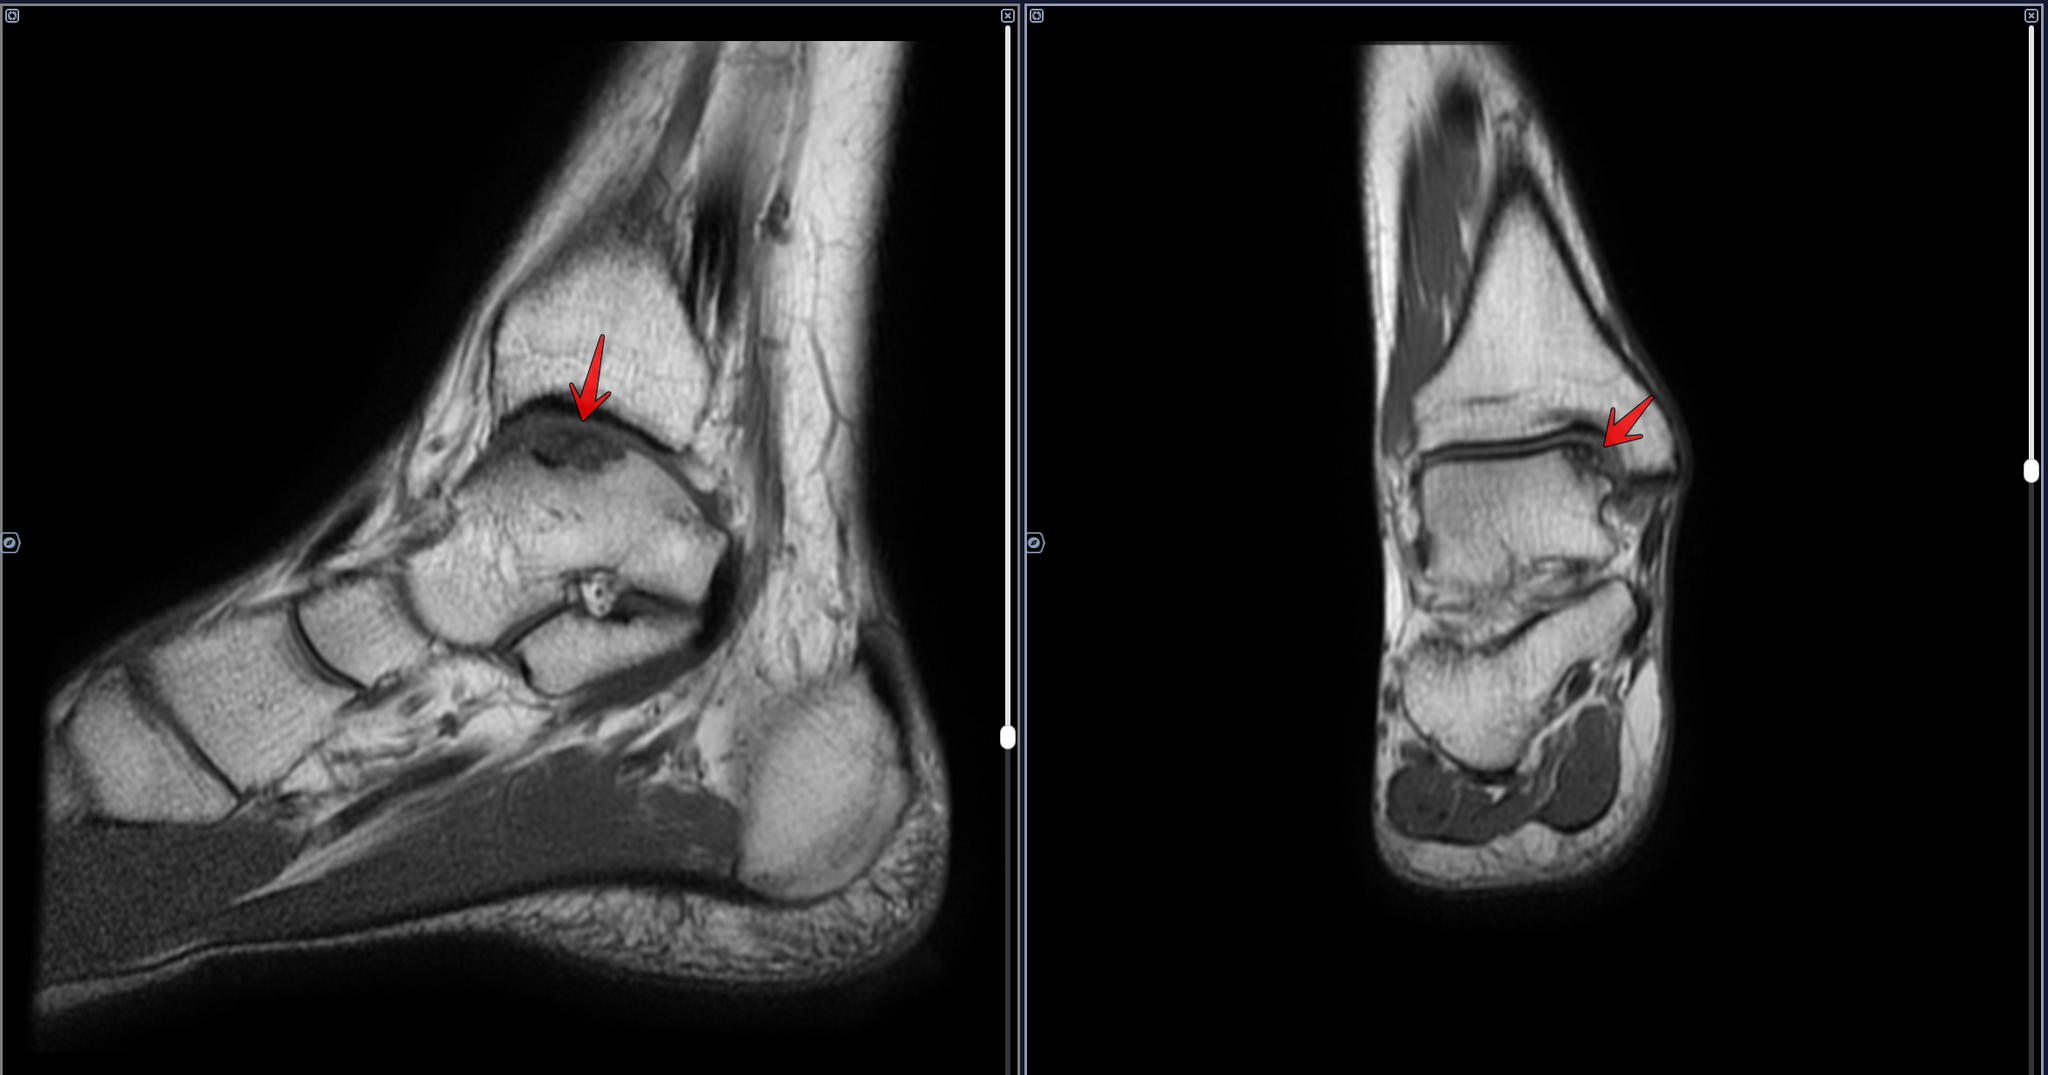

Кейс призывника с рассекающим остеохондритом(б.Кенига) таранной кости(КТ+МРТ)

Призывником были выполнены КТ И МРТ правого голеностопного сустава в частных клиниках.

Описание КТ: по верхне-внутреннему контуру суставной пластинки таранной кости определяется фрагментация кости в виде сгруппированных фрагментов на участке 11х5х6 мм, в ложе кости, отграниченным ободком остеосклероза до 3 мм шириной, перифокально кистовидная перестройка губчатой кости. Заключение: Рассекающий остеохондрит правой таранной кости 3-4 ст.